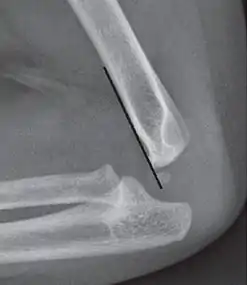

The anterior humeral line is not reliable in children with sparse ossification of the capitulum, such as in this 6 months old child.[8]